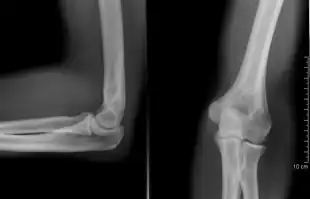

Projectional radiography

The creation of images by exposing an object to X-rays or other high-energy forms of electromagnetic radiation and capturing the resulting remnant beam (or "shadow") as a latent image is known as "projection radiography". The "shadow" may be converted to light using a fluorescent screen, which is then captured on photographic film, it may be captured by a phosphor screen to be "read" later by a laser (CR), or it may directly activate a matrix of solid-state detectors (DR—similar to a very large version of a CCD in a digital camera). Bone and some organs (such as lungs) especially lend themselves to projection radiography. It is a relatively low-cost investigation with a high diagnostic yield. The difference between soft and hard body parts stems mostly from the fact that carbon has a very low X-ray cross section compared to calcium.